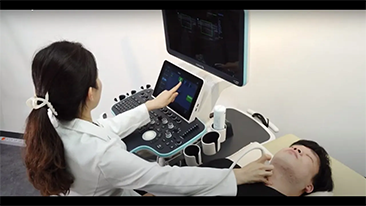

Mit den allgemeinen Bildgebungsl?sungen der Resona-Serie von Mindray k?nnen Arzt und ?rztin genauer und effizienter diagnostizieren sowie bessere Behandlungserfolge erzielen, durch umfassende geteilte Anwendung der Sonden und effiziente klinische Anwendungstools.